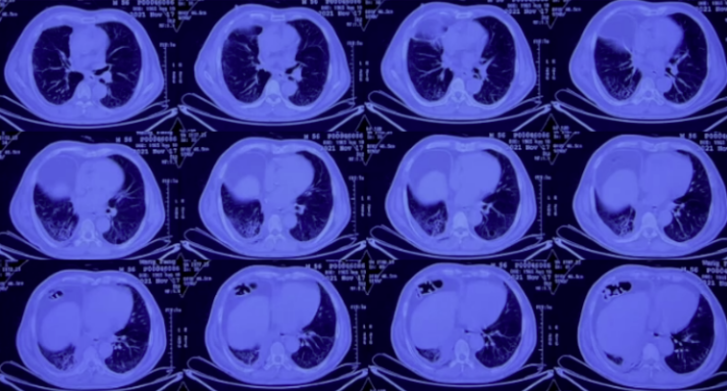

复查胸部CT(2021-12-27):右肺有大片蜂窝状改变,右下肺有脓胸、空洞及纵隔脓肿(图6)。

图6 复查胸部CT(2021-12-27)